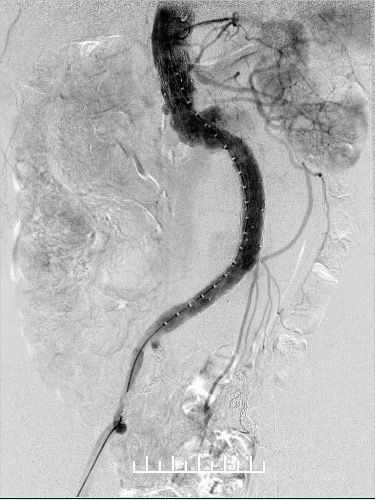

使用全穿刺技术(Preclose技术),建立双侧股动脉及右侧肱动脉入路。“全身像”显示:瘤颈成角约90度,左侧髂总动脉钙化扭曲严重,双侧髂内动脉显影,左侧髂内动脉瘤。